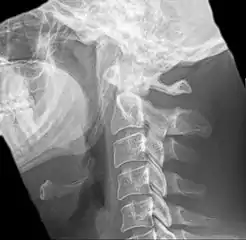

Radiograph, lateral view showing elongated stylohyoid process and stylohyoid ligament ossification

Imaging is important and is diagnostic. Visualizing the styloid process on a CT scan with 3D reconstruction is the suggested imaging technique.[12] The enlarged styloid may be visible on an orthopantogram or a lateral soft tissue X ray of the neck.